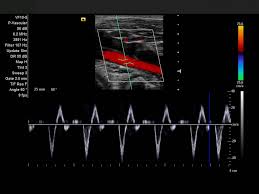

Импульсно-волновой (PW) и постоянно-волновой (CW) допплер. Позволяют проводить количественную оценку кровотока. PW-допплер используется для оценки сосудистых скоростей в конкретной анатомической зоне, в то время как CW-допплер применяется для измерения высокоскоростного потока, например, при оценке клапанных патологий сердца.

Высокочастотный импульсный допплер (HPRF). Увеличивает диапазон измеряемых скоростей при сохранении точности локализации, что критично при исследовании глубоких или быстро движущихся сосудистых структур, особенно в абдоминальной и сосудистой визуализации.